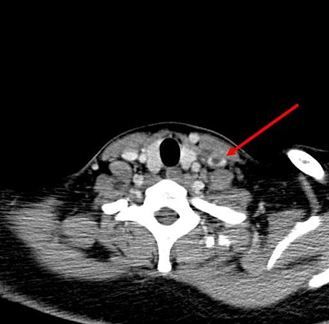

Fig 4. CT neck; thrombus in left internal jugular vein.

Later, a CT scan of the neck was performed. Results showed mild nonspecific thickening of the left tonsillar pillar and a thrombus in left internal jugular vein (Figures 2, 3, and 4, click to enlarge).